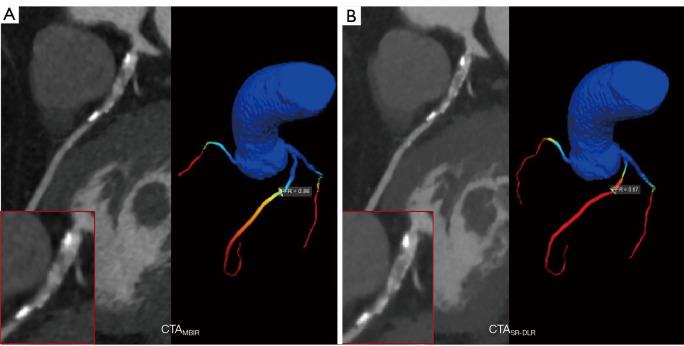

Super-resolution deep learning reconstruction (SR-DLR) algorithm has emerged as a promising image reconstruction technique for improving the image quality of coronary computed tomography angiography (CCTA) and ensuring accurate CCTA-derived fractional flow reserve (CT-FFR) assessments even in problematic scenarios (e.g., the presence of heavily calcified plaque and stent implantation). Therefore, the purposes of this study were to evaluate the image quality of CCTA obtained with SR-DLR in comparison with conventional reconstruction methods and to investigate the diagnostic performances of different reconstruction approaches based on CT-FFR.

SR-DLR achieved the lowest image noise, highest signal-to-noise ratio (SNR), and best edge sharpness (all P values <0.05), as well as the best subjective scores from both reviewers (all P values <0.001). With FFR serving as a reference, the specificity and positive predictive value (PPV) were improved as compared with HIR and C-DLR (72% 36-44% and 73% 53-58%, respectively); moreover, SR-DLR improved the sensitivity and negative predictive value (NPV) as compared to MBIR (95% 70% and 95% 68%, respectively; all P values <0.05). The overall diagnostic accuracy and area under the curve (AUC) for SR-DLR were significantly higher than those of the HIR, MBIR, and C-DLR algorithms (82% 60-67% and 0.84 0.61-0.70, respectively; all P values <0.05).

SR-DLR had the best image quality for both objective and subjective evaluation. The diagnostic performances of CT-FFR were improved by SR-DLR, enabling more accurate assessment of flow-limiting lesions.

超分辨率深度学习重建(SR-DLR)算法已成为一种很有前景的图像重建技术,可用于提高冠状动脉计算机断层扫描血管造影(CCTA)的图像质量,并确保即使在存在问题的情况下(例如,存在严重钙化斑块和支架植入)也能准确进行基于CCTA的血流储备分数(CT-FFR)评估。因此,本研究的目的是比较SR-DLR与传统重建方法获得的CCTA图像质量,并基于CT-FFR研究不同重建方法的诊断性能。

SR-DLR实现了最低的图像噪声、最高的信噪比(SNR)和最佳的边缘清晰度(所有P值<0.05),以及两位阅片者给出的最佳主观评分(所有P值<0.001)。以FFR作为参考,与HIR和C-DLR相比,特异性和阳性预测值(PPV)有所提高(分别为72%对36%-44%和73%对53%-58%);此外,与MBIR相比,SR-DLR提高了敏感性和阴性预测值(NPV)(分别为95%对70%和95%对68%;所有P值<0.05)。SR-DLR的总体诊断准确性和曲线下面积(AUC)显著高于HIR、MBIR和C-DLR算法(分别为82%对60%-67%和0.84对0.61-0.70;所有P值<0.05)。

SR-DLR在客观和主观评估方面均具有最佳图像质量。SR-DLR提高了CT-FFR的诊断性能,能够更准确地评估限流性病变。